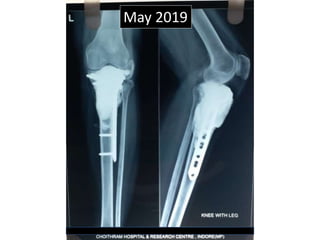

The document discusses a case involving a pathological fracture of the upper tibia, treated at Choithram Hospital in Indore, India. Postoperative complications included gas collection under the wound after excessive cementing, though no infection was present, and the patient required careful follow-up. The patient showed progress in recovery, with mobilization using a walker initiated after six weeks.